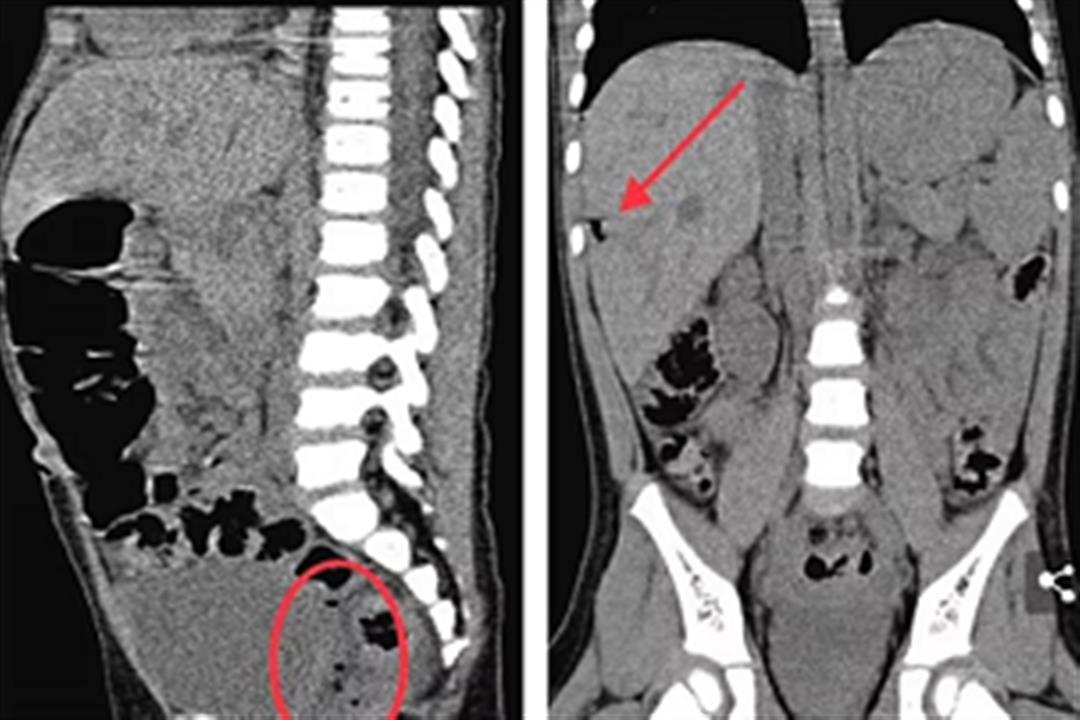

وأظهرت الموجات فوق الصوتية وجود جسم غريب في الكبد، أدى إلى تورم هذه المنطقة وتراكم الصديد بها.

تم إعطاء الطفلة المضادات الحيوية، وقرر الأطباء إجراء العملية مرة أخرى، حيث وجدوا جزءًا من الحفاض مقاس 7 مم في 7 مم متصلًا بالكبد، فقاموا بإزالته على الفور، مما أدى إلى تصريف الصديد المحيط به.